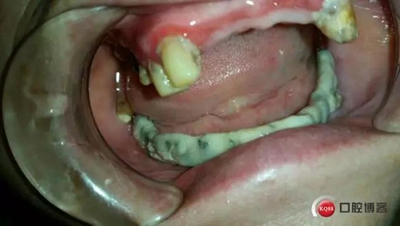

開(kāi)嘴效果